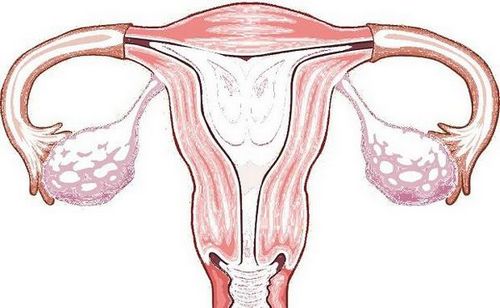

Лікарі стверджують, що причиною виникнення подібних відчуттів є збільшення матки в розмірах. Даний орган активно розтягується і видозмінюється іменнона ранніх термінах вагітності, через що і виникають поколювання. Відбувається це, як правило, між 5 і 8 тижнями (може спостерігатися і дещо пізніше), коли матка змінює свою форму з грушоподібної на яйцеподібну.

Саме яйцеподібна форма матки вважається оптимальною для нормального розвитку плода і тому м'язам необхідно постійно її підтримувати. Однак напруга, в якому знаходяться м'язи, що підтримують матку, не може пройти безслідно, вони розтягуються і жінка відчуває поколювання. Причому, як показує практика, більшість майбутніх матусь відчувають неприємні поколювання при різких рухах, при кашлі або чханні.

Буквально через 30 днів майбутню маму можуть турбувати досить сильні поколювання в матці. Пов'язано це зі зміною її форми - судини переповнюються кров'ю, орган округляється і збільшується. Змінюється структура шийки матки - вона стає більш еластичною і м'якою. Неприємні відчуття спостерігаються в нижній частині живота. У деяких вагітних поколювання в матці викликає дискомфорт і супроводжується болями, що тягнуть, чимось нагадують дні перед менструацією.

Причин для паніки насправді немає, якщо тільки поколювання не тривають весь день. Найчастіше вони відчуваються при зміні положення торсу, різких рухах і чханні. Незважаючи на те що поколювання в матці носить природний характер, жінці хочеться швидше усунути цей стан. Деякі намагаються прийняти зручне положення, інші більше рухаються, здійснюють прогулянки, відвідують басейн і фітнес для вагітних. Найбільш ефективним способом є заняття на м'ячі - вправи допоможуть зміцнити м'язи малого тазу. Подібні тренування показані не всім.